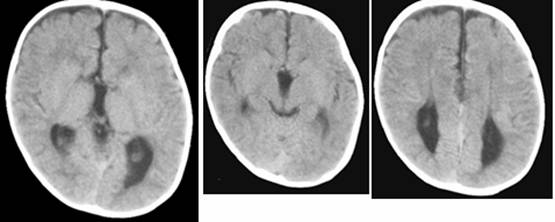

Figure 5

Clinical and image aspects of patient 5

Int J Med Sci Image